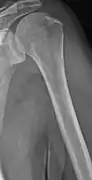

Multiple myeloma in the upper arm

Humerus with multiple myeloma lesions

Same humerus before, with just subtle lesions